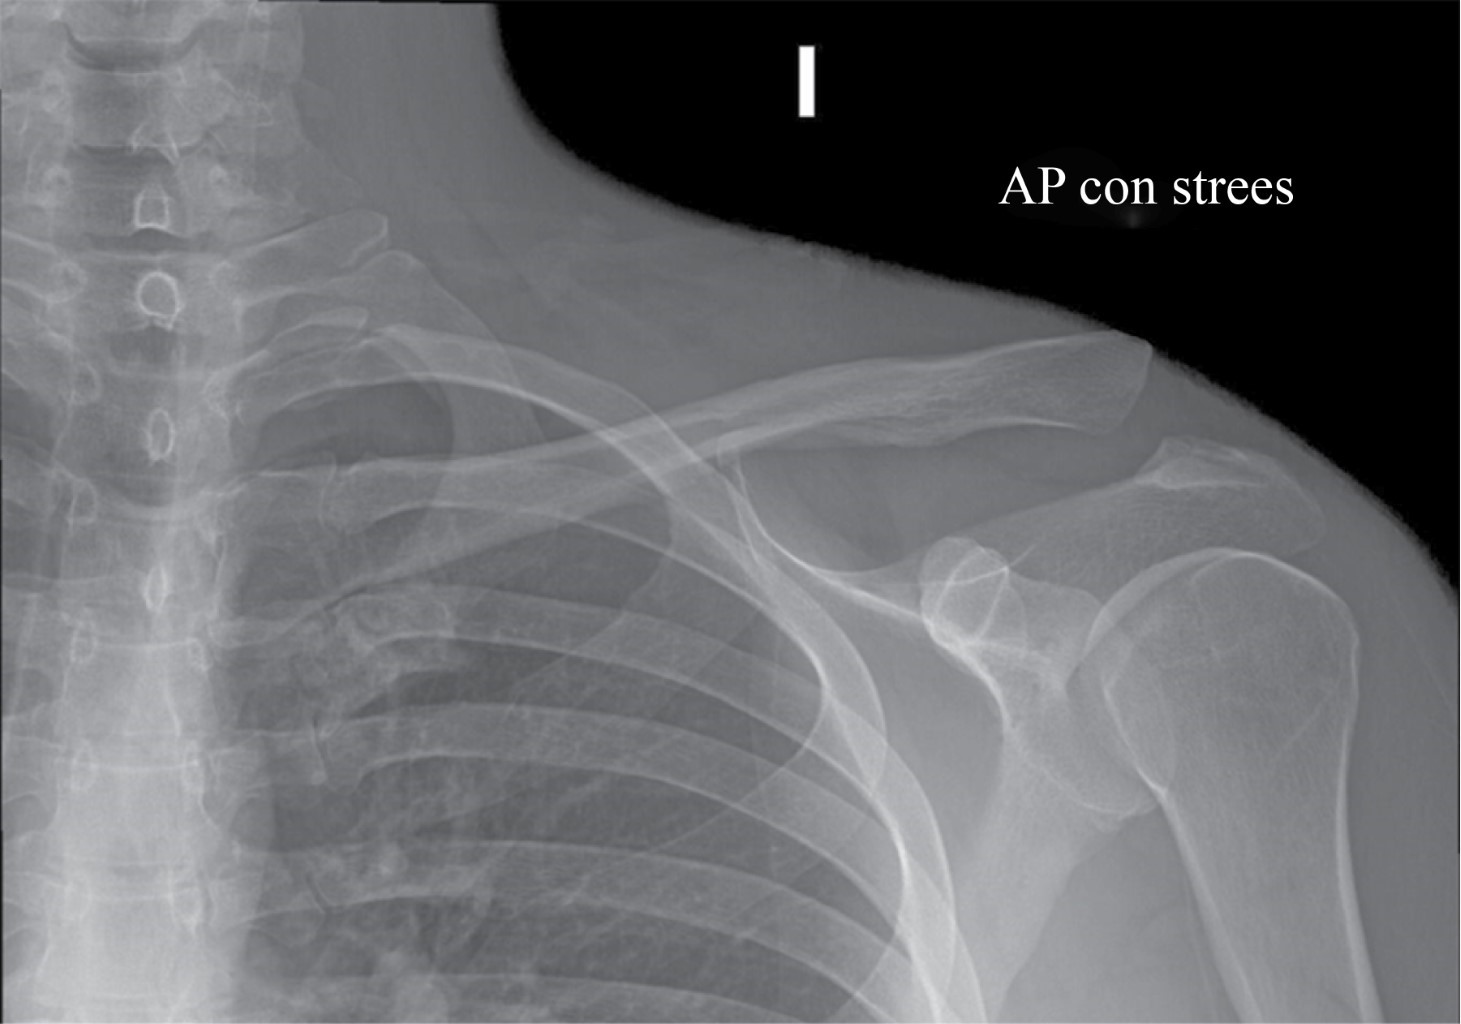

El objetivo de nuestra técnica quirúrgica es restaurar la estabilidad tanto vertical como horizontal de la articulación acromioclavicular (AC) mediante el uso de una técnica abierta de reconstrucción de la articulación AC con aloinjerto (semitendinoso o peroneus longus) para restaurar la estabilidad horizontal. Se realiza una reconstrucción anatómica de los ligamentos CC utilizando aloinjerto y fijación con dos tornillos de biotenodesis. En cuatro pacientes con diagnóstico de luxación AC grado III-V según la clasificación de Rockwood, clínicamente son pacientes con alta demanda funcional que presentaron un mecanismo de lesión de contusión directa con carga axial y brazo en aducción del hombro; posteriormente muestran deformidad en el tercio distal de la clavícula, con dolor en la articulación AC y limitación para la abducción del hombro y elevación del brazo. Mediante radiografías anteroposterior de hombro comparativas con carga y axial de hombro se hicieron los diagnósticos de luxación AC Rockwood III-V (Figura 1), por lo que se procede a realizar cirugía en etapa aguda.

Figura 1